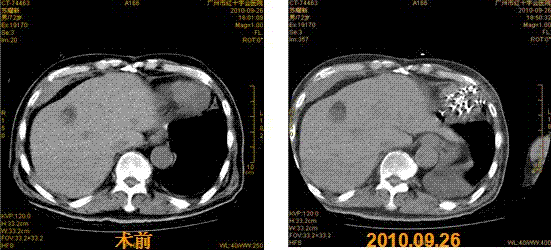

2013年8月底,经朋友介绍慕名来到广州中医药大学金沙洲医院肿瘤中心接受WB-1全身热疗(肿瘤深部全身热疗),根据患者的情况,专家团会诊后采用全身热疗结合P53基因治疗,1个疗程后,肺部肿瘤缩小42.7%,疼痛、咳嗽、腹水等症状全面消失,白细胞上升到正常水平。近期回访,患者身体状况良好,达到带瘤生存。